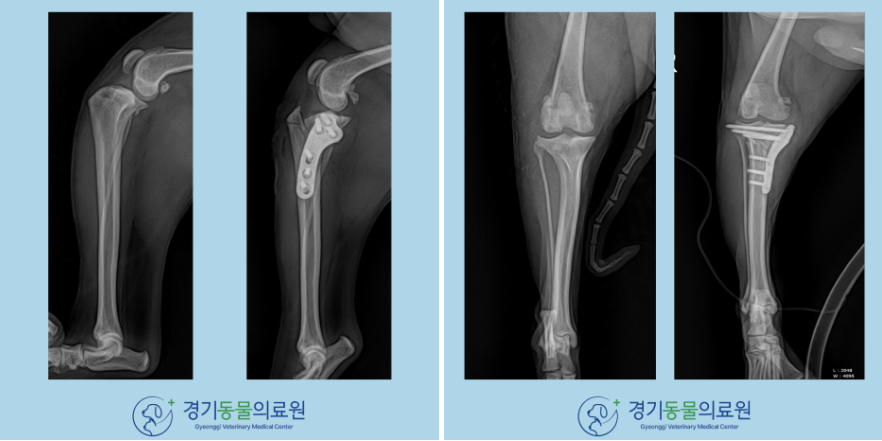

​곰*의 경우에는 TPLO수술 진행해주었습니다.

​모식도에서 확인할 수 있듯이 TPLO수술은 절골술을 통해 경골고원각(TPA)를 낮춰주는 방법입니다.

​계획한 대로 수술이 진행되었고, 수술 후 고원각의 감소가 확인됩니다.